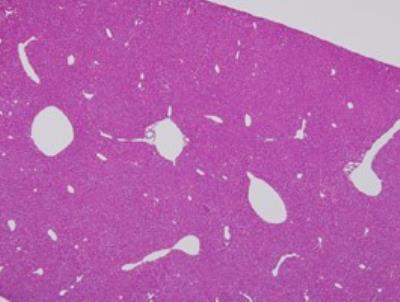

I think these maybe brain cells.

BRAIN CELL EXAMPLES

BRAIN CELLS:

All of these photos are not mine. the labels on the larger photo above these two are not mine either.

Brain cells found in my slides:

A lot of these look a little bit different but I think these are brain cells.

I’m sorry about the shadow on the sides of the photos. I think this has something to do with the microscope’s objective lens, which I have tried to clean, but I can’t fix it.

These a look a little bit different than the ones above, so I am not 100% sure that they are the same type of cells.